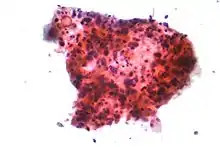

Performing a chest radiograph is one of the first investigative steps if a person reports symptoms that may be suggestive of lung cancer. This may reveal an obvious mass, the widening of the mediastinum (suggestive of spread to lymph nodes there), atelectasis (lung collapse), consolidation (pneumonia), or pleural effusion.[7] CT imaging of the chest may reveal a spiculated mass which is highly suggestive of lung cancer, and is also used to provide more information about the type and extent of disease. Bronchoscopic or CT-guided biopsy is often used to sample the tumor for histopathology.[17]

Lung cancers are classified according to histological type.[6] This classification is important for determining both the management and predicting outcomes of the disease. Lung cancers are carcinomas – malignancies that arise from epithelial cells. Lung carcinomas are categorized by the size and appearance of the malignant cells seen by a histopathologist under a microscope. For therapeutic purposes, two broad classes are distinguished: non-small-cell lung carcinoma and small-cell lung carcinoma.[70]